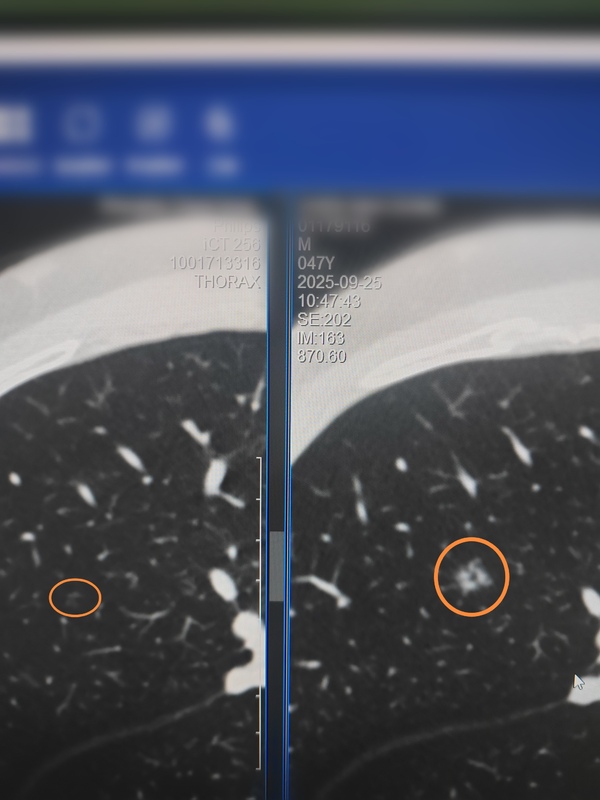

一般而言从5mm以内纯磨玻璃结节的不典型增生长到10mm左右的微浸润性腺癌的时间是非常长的。但如果微小纯磨玻璃结节在随访中出现了实性成份或密度明显增高需要警惕这种结节可能不再走寻常路,而很可能会加速进展。就像该例结节从2mm左右的纯磨玻璃长到8mm的微浸润性腺癌仅用了6年多的时间,向前追踪发现该结节在后续随访中出现了明显的实性成份,说明其恶性程度较高,是不同寻常的“激进分子”这类结节是少数,但我们不可不防,其实规律复查才是关键。